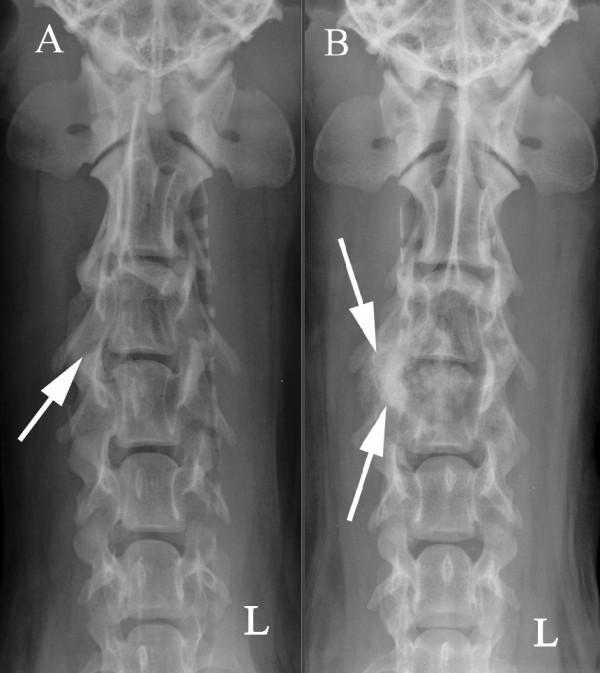

A ten-year-old male standard dachshund was presented with a history of neck pain and progressive gait disturbances. Following a neurological examination and diagnostic imaging, including CT, a neoplastic lesion involving the third and fourth cervical vertebrae was suspected. The lesion included an extradural mass on the right side of the spinal canal causing a local compression of the cervical cord. Surgery, using a modified dorsal laminectomy procedure, was performed in order to decompress the cervical spinal cord. Histopathological examination of the extradural mass indicated that the tumour was a chondroid chordoma. Following discharge, the quality of life for the dog was very good for a sustained period, but clinical signs recurred at 22 months. The dog was euthanased 25 months post-surgery. On post-mortem examination, a regrowth of neoplastic tissue was found to have infiltrated the bone and spinal cord at C3-C4. This is the first report to show that palliative surgery can offer successful long-lasting treatment of chondroid chordoma of the cervical spine in the dog.

一只十岁大的雄性标准贵宾犬,出现颈部疼痛和进行性步态障碍的病史。经过神经学检查和包括 CT 在内的诊断影像学检查后,怀疑第三和第四颈椎有肿瘤病变。病变包括椎管右侧的硬膜外肿块,导致颈脊髓局部受压。为了对颈脊髓进行减压,采用改良的背侧椎板切除术进行了手术。硬膜外肿块的组织病理学检查表明肿瘤为软骨脊索瘤。出院后,狗狗的生活质量在很长一段时间内都非常好,但在 22 个月时临床症状再次出现。手术后 25 个月,狗狗被实施了安乐死。尸检时发现,C3-C4 处的骨和脊髓有肿瘤组织再生并浸润。这是首例报道显示姑息性手术可以为犬颈椎软骨脊索瘤提供成功的长期治疗。